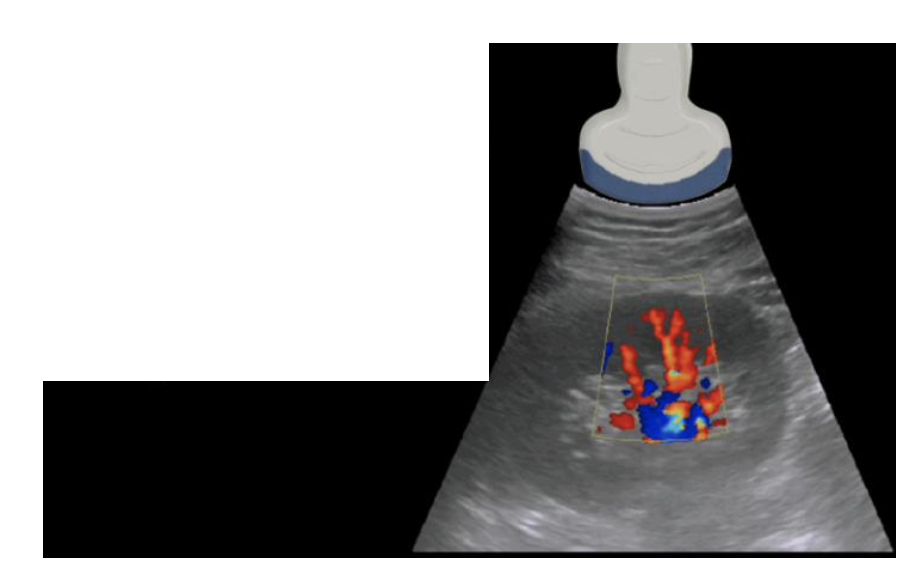

Power Doppler Mode

• -PD is more sensitive than color Doppler and is used to detect low flow states such as venous flow in the thyroid or testicles

• Displays the amplitude (strength) of blood flow signals rather than velocity or direction.

• More sensitive to low-velocity or small vessel flow than colour Doppler.

• Does not provide directionality of flow, but reduces angle dependency and is less affected by aliasing.

Power Doppler (PD) Mode in MSK

ultrasound

• PD is more sensitive than color Doppler and is used to detect blood flow or

vascularity in tendons

• Increased PD signals are associated with inflammatory conditions.

• Doppler signals are easily obliterated with probe pressure or when the

tendon is stretched